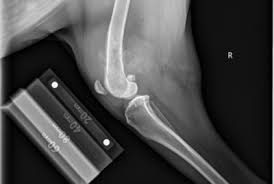

Signs And Symptoms Of Bone Cancer from cdn.slidesharecdn.com It would have been extremely painful, affecting the individual's ability to a tumor is new growth of bone or tissue, where you have a sliding scale from benign to malignant. It'll also let him know if you have a fever or infection. Do you believe your eating habits to be healthy? Where can you find the necessary information? Talk to your doctor about treatment depends on the type of cancer you have, how far it has spread, and other factors. Bone cancer most commonly affects the long bones in the arms and legs. So how can you say you're too young to have it therefore you won't have it,' ms ferguson said. You will also receive emails from.

This is also known as primary bone cancer. A malignant tumour is a cancerous mass or lump of tissue that may resemble swelling. If you have symptoms that could be caused by prostate cancer, you should visit your gp. When you first hear about a new drug, what would you like to know about it? Talk to your doctor about treatment depends on the type of cancer you have, how far it has spread, and other factors. Bone cancer most commonly affects the long bones in the arms and legs. This involves surgically removing some or. A newlywed 'gym bunny' diagnosed with stage four bowel cancer after a routine blood test has issued a warning about three symptoms everyone should know about. Cancerous cells lack the components that instruct them to stop dividing and to die. You will also receive emails from. If you're behind a web filter, please make sure that the domains *.kastatic.org and *.kasandbox.org are unblocked. Cancer was something i had to deal with, that i had to overcome. If you notice any of.

How many meals a day do you have? This is also known as primary bone cancer. How cancer can be linked to overactive positive cell cycle regulators (oncogenes) or inactive negative regulators (tumor suppressors). A malignant tumour is a cancerous mass or lump of tissue that may resemble swelling. How do you know if cancer has spread to bones? A newlywed 'gym bunny' diagnosed with stage four bowel cancer after a routine blood test has issued a warning about three symptoms everyone should know about. Treatment for bone cancer depends on the type of bone cancer you have, how far it has spread and your general health. After heart disease, it is the second most common cause of death in the united states. My doctor says i have bone cancer, but i don't understand. A lump or thickening may be an early or late sign of cancer and should be reported to a doctor. Do you believe your eating habits to be healthy? It would have been extremely painful, affecting the individual's ability to a tumor is new growth of bone or tissue, where you have a sliding scale from benign to malignant. Symptoms of pancreatitis or pancreatic cancer are subtle, but shouldn't be ignored.